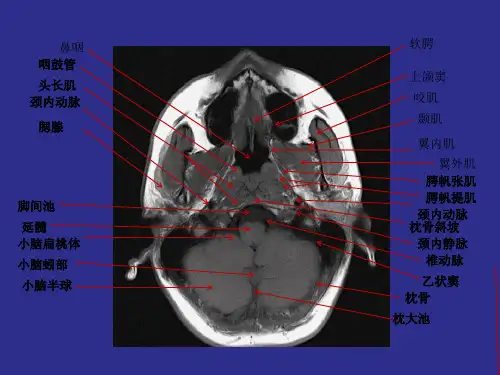

鼻咽部解剖

咽鼓管 、咽鼓管咽口 咽鼓管隆突 咽隐窝(位于颅底破裂孔

下面,中间无明显结构, 鼻咽癌若发生于咽隐窝, 容易侵犯破裂孔向颅内蔓 延)

鼻咽介于 颅底-硬 腭之间 咽颅底筋膜

前:鼻腔、翼腭窝 后:增殖腺(咽扁

桃体或增殖体 两侧:咽旁间隙 顶:蝶骨体、斜坡、